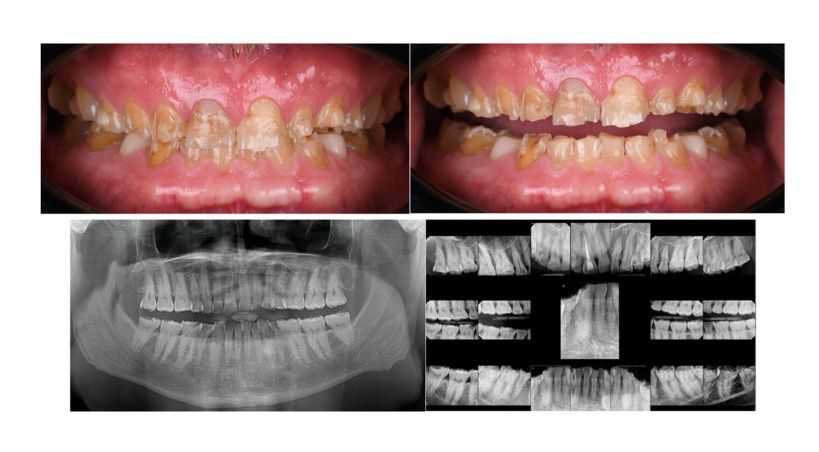

Materiales restauradores bioactivos en odontología

Una revisión integral de los mecanismos, aplicaciones clínicas y direcciones futuras